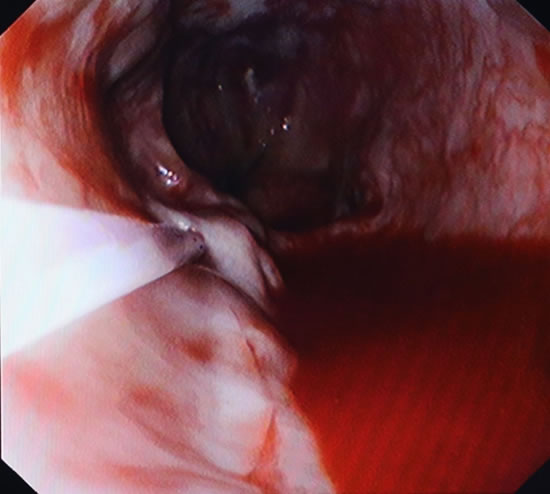

郎溪县人民医院成功开展了胃镜下食管静脉曲张硬化术

郎溪县人民医院消化内科与南京中大医院协作,成功开展了胃镜下食管静脉曲张硬化术。该技术适用于肝硬化合并食管静脉曲张破裂出血及预防再出血患者,减少患者反复出血带来的痛苦,提高生存质量。